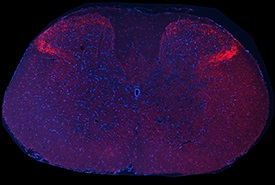

Images